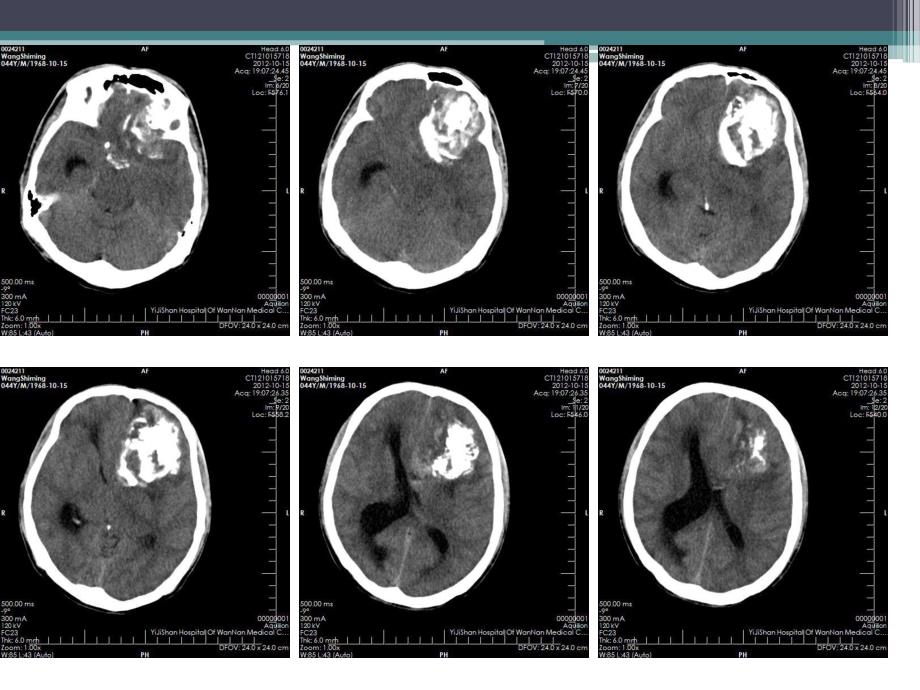

1、病例1男,44岁。主诉:头晕十余天,加重一天。查体:神清,嗜睡,四肢肌力IV级,余无 特殊。病理诊断:病理诊断:(左侧额叶)间变型少突胶质星形细胞瘤(相当于WHO 级)。免疫组化标记结果,瘤细胞:LCA(-)、AE1/AE3(-)、p53(-)、EMA(-)、S-100(+)、CD34(-)、GFAP(+)、PR(-)、Ki-67:5%(+)。概念:概念:2007年WHO颁布的分类方法巾,少突胶质细胞起源的肿瘤(oligodendroglial tumours)属于神经上皮性肿瘤,分为少突胶质细胞瘤(oligodendroglioma,grade II)和间变性少突胶质细胞瘤(anaplast

2、icoligodendroglioma,grade)。少突胶质细胞起源的肿瘤占成人脑胶质瘤的33%,是继多形性胶质母细胞瘤之后,第二位的成人脑胶质瘤。相对于同级别的星形细胞瘤而言,少突胶质细胞瘤的临床过程较长,预后较好。85%位于幕上,好发于额叶,表浅部位 发病高峰3545岁,病程较长 男性稍多于女性 临床表现:病人以长时间局灶性癫痫为首发症状,其他症状和体征以肿瘤的发生部位而定。病理特征:病理特征:镜下肿瘤细胞呈蜂窝状,细胞大小、形态相似,排列均匀一致,细胞核呈规则球形,核周透明空泡环绕形成“煎蛋样”形态,间质少,间质内散布丰富的树杈样或鹿角样血管,常有钙化,常发生于肿瘤血管壁上,亦可发生于

3、肿瘤内或瘤外组织。影像学表现:CT:平扫平扫多数呈低密度,少数略高 钙化多见,典型者表现为弯曲条状钙化灶占肿瘤大部 囊变、出血少见 占位效应轻,无水肿或轻度水肿增强增强大多数无强化,少数轻度强化MRIMRI平扫平扫长或等T1长T2 钙化在T1/T2上均呈低信号 肿瘤多为圆形或椭圆形,边界清楚,瘤周水肿无或轻度,占位效应轻。增强增强无或轻度强化鉴别诊断鉴别诊断 血管母细胞瘤:平扫很难鉴别,增强明显。MR可见血管留空效应?钙化?毛细胞型星形细胞瘤:常发生于颞叶,囊变多见。节细胞瘤:常发生于颞叶,囊变、钙化常见。脑膜瘤 室管膜瘤病例2男,70岁。主诉:记忆力减退待查。查体:神清,精神可。病理结果:病